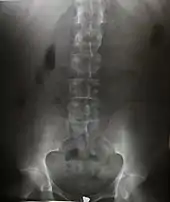

AP radiograph of the lumbar spine